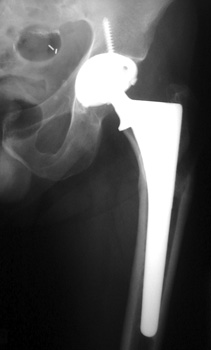

FEMORAL STEM POSITION

• Valgus positioning

Varus Normal Valgus

Valgus